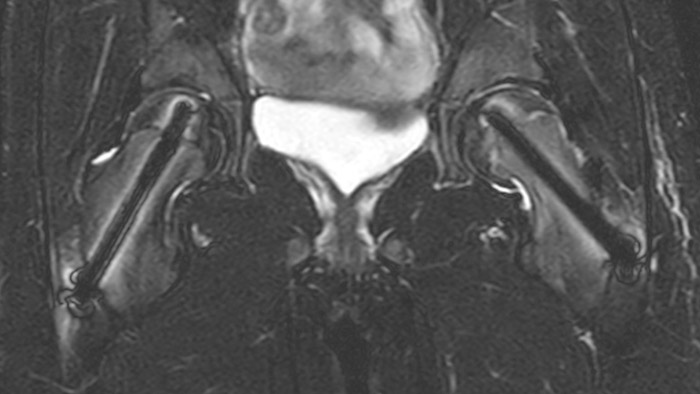

Slipped capital femoral epiphysis

After intervention with two cannulated titan screws, it is important to check that the circumference is normal and without necrosis. The screws can cause major metal artifacts, but O-MAR allows to improve visualization of tissue and bone in the near vicinity of MR Conditional orthopedic implants1. 1 Only for use with MR Safe or MR Conditional implants by strictly following the Instructions for Use

Perthes disease in left hip The affected area on the upper circumference of the left hip shows contrast uptake in the dynamic scan. The radial scan nicely depicts the hip area, despite the dark shape in the center that is inherent to the radial way of scanning.